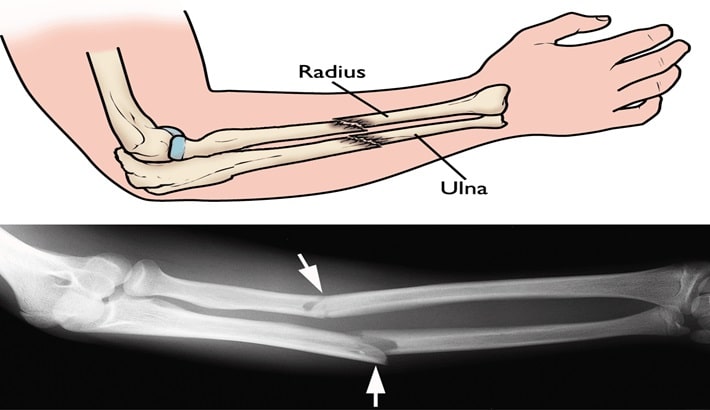

۱. شکستگیهای دست و مچ:

شکستگیهایی مانند شکستگی استخوان اسکافوید (ناوی) در مچ، یا شکستگیهای متاکارپال (مشابه مشت زدن) نیازمند دقت بسیار در توانبخشی هستند. بیحرکتی طولانیمدت پس از گچگیری یا جراحی میتواند منجر به خشکی مفاصل، آتروفی عضلانی و ایجاد چسبندگی در تاندونها شود. هندتراپی با زمانبندی دقیق، مانع از این عوارض و تسهیلکننده جوشخوردگی صحیح است.